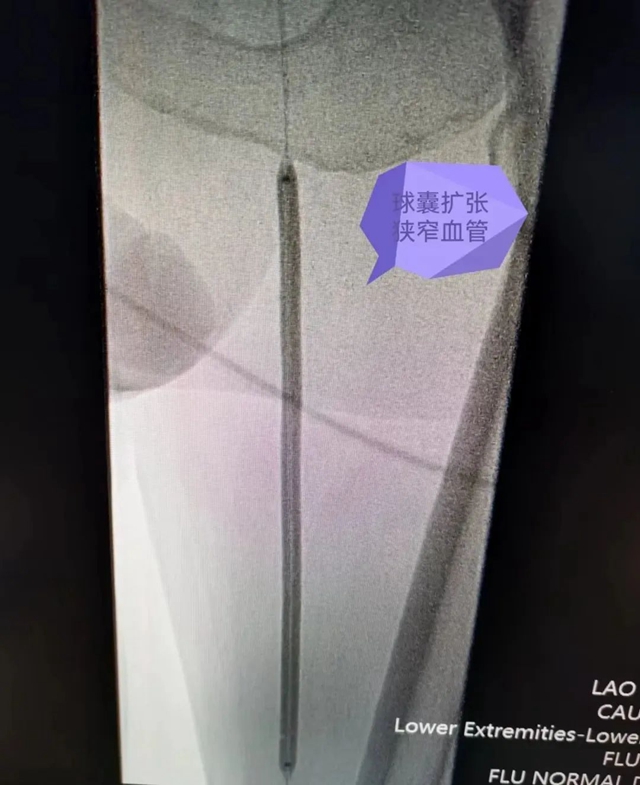

术中对狭窄段进行球囊扩张

患者蔡叔叔(化名)有长达10余年的糖尿病史,血糖控制效果不佳。3个月前右足溃烂流脓,疼痛难忍,便到合江县中医医院就诊,因右足溃烂流脓收入骨伤科住院治疗,经介入医学中心负责人鞠新强会诊后,结合蔡叔叔下肢血管CTA,诊断为双下肢动脉闭塞症,符合介入开通血管指征,无绝对介入手术禁忌症。由于蔡叔叔有精神病史,与家属沟通后,于2022年10月27在全麻下行“双下肢动脉造影+球囊扩张成行术+支架植入术”。

经过约3小时手术,蔡叔叔闭塞血管开通,安全返回病房继续治疗。术后右下肢皮温逐步恢复,麻木、疼痛有所缓解,可逐步下床行走,成功避免了截肢的风险。

患者术前双下肢血管CTA:右侧髂总动脉起始段狭窄,左侧股浅动脉狭窄,下段闭塞。